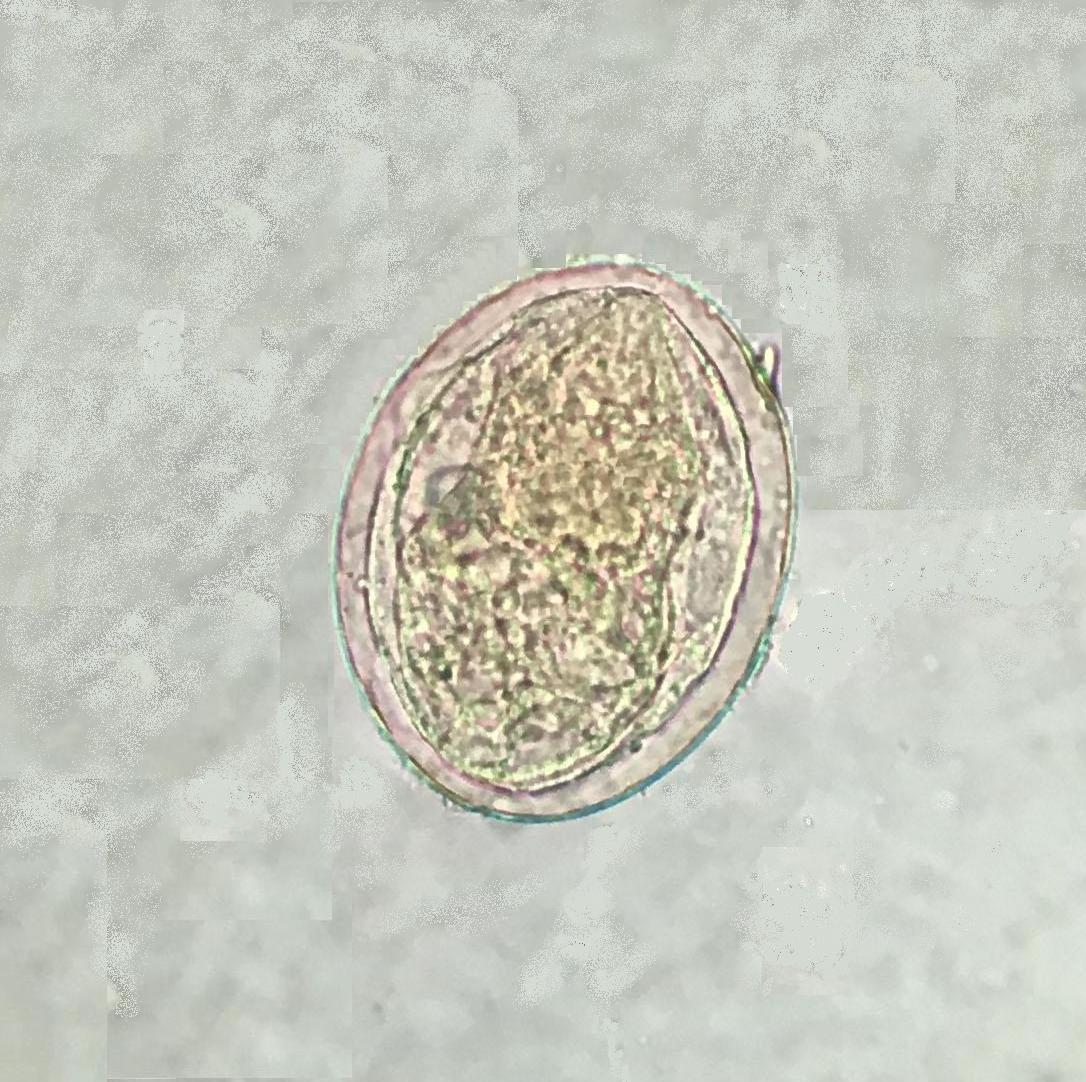

裂体吸虫